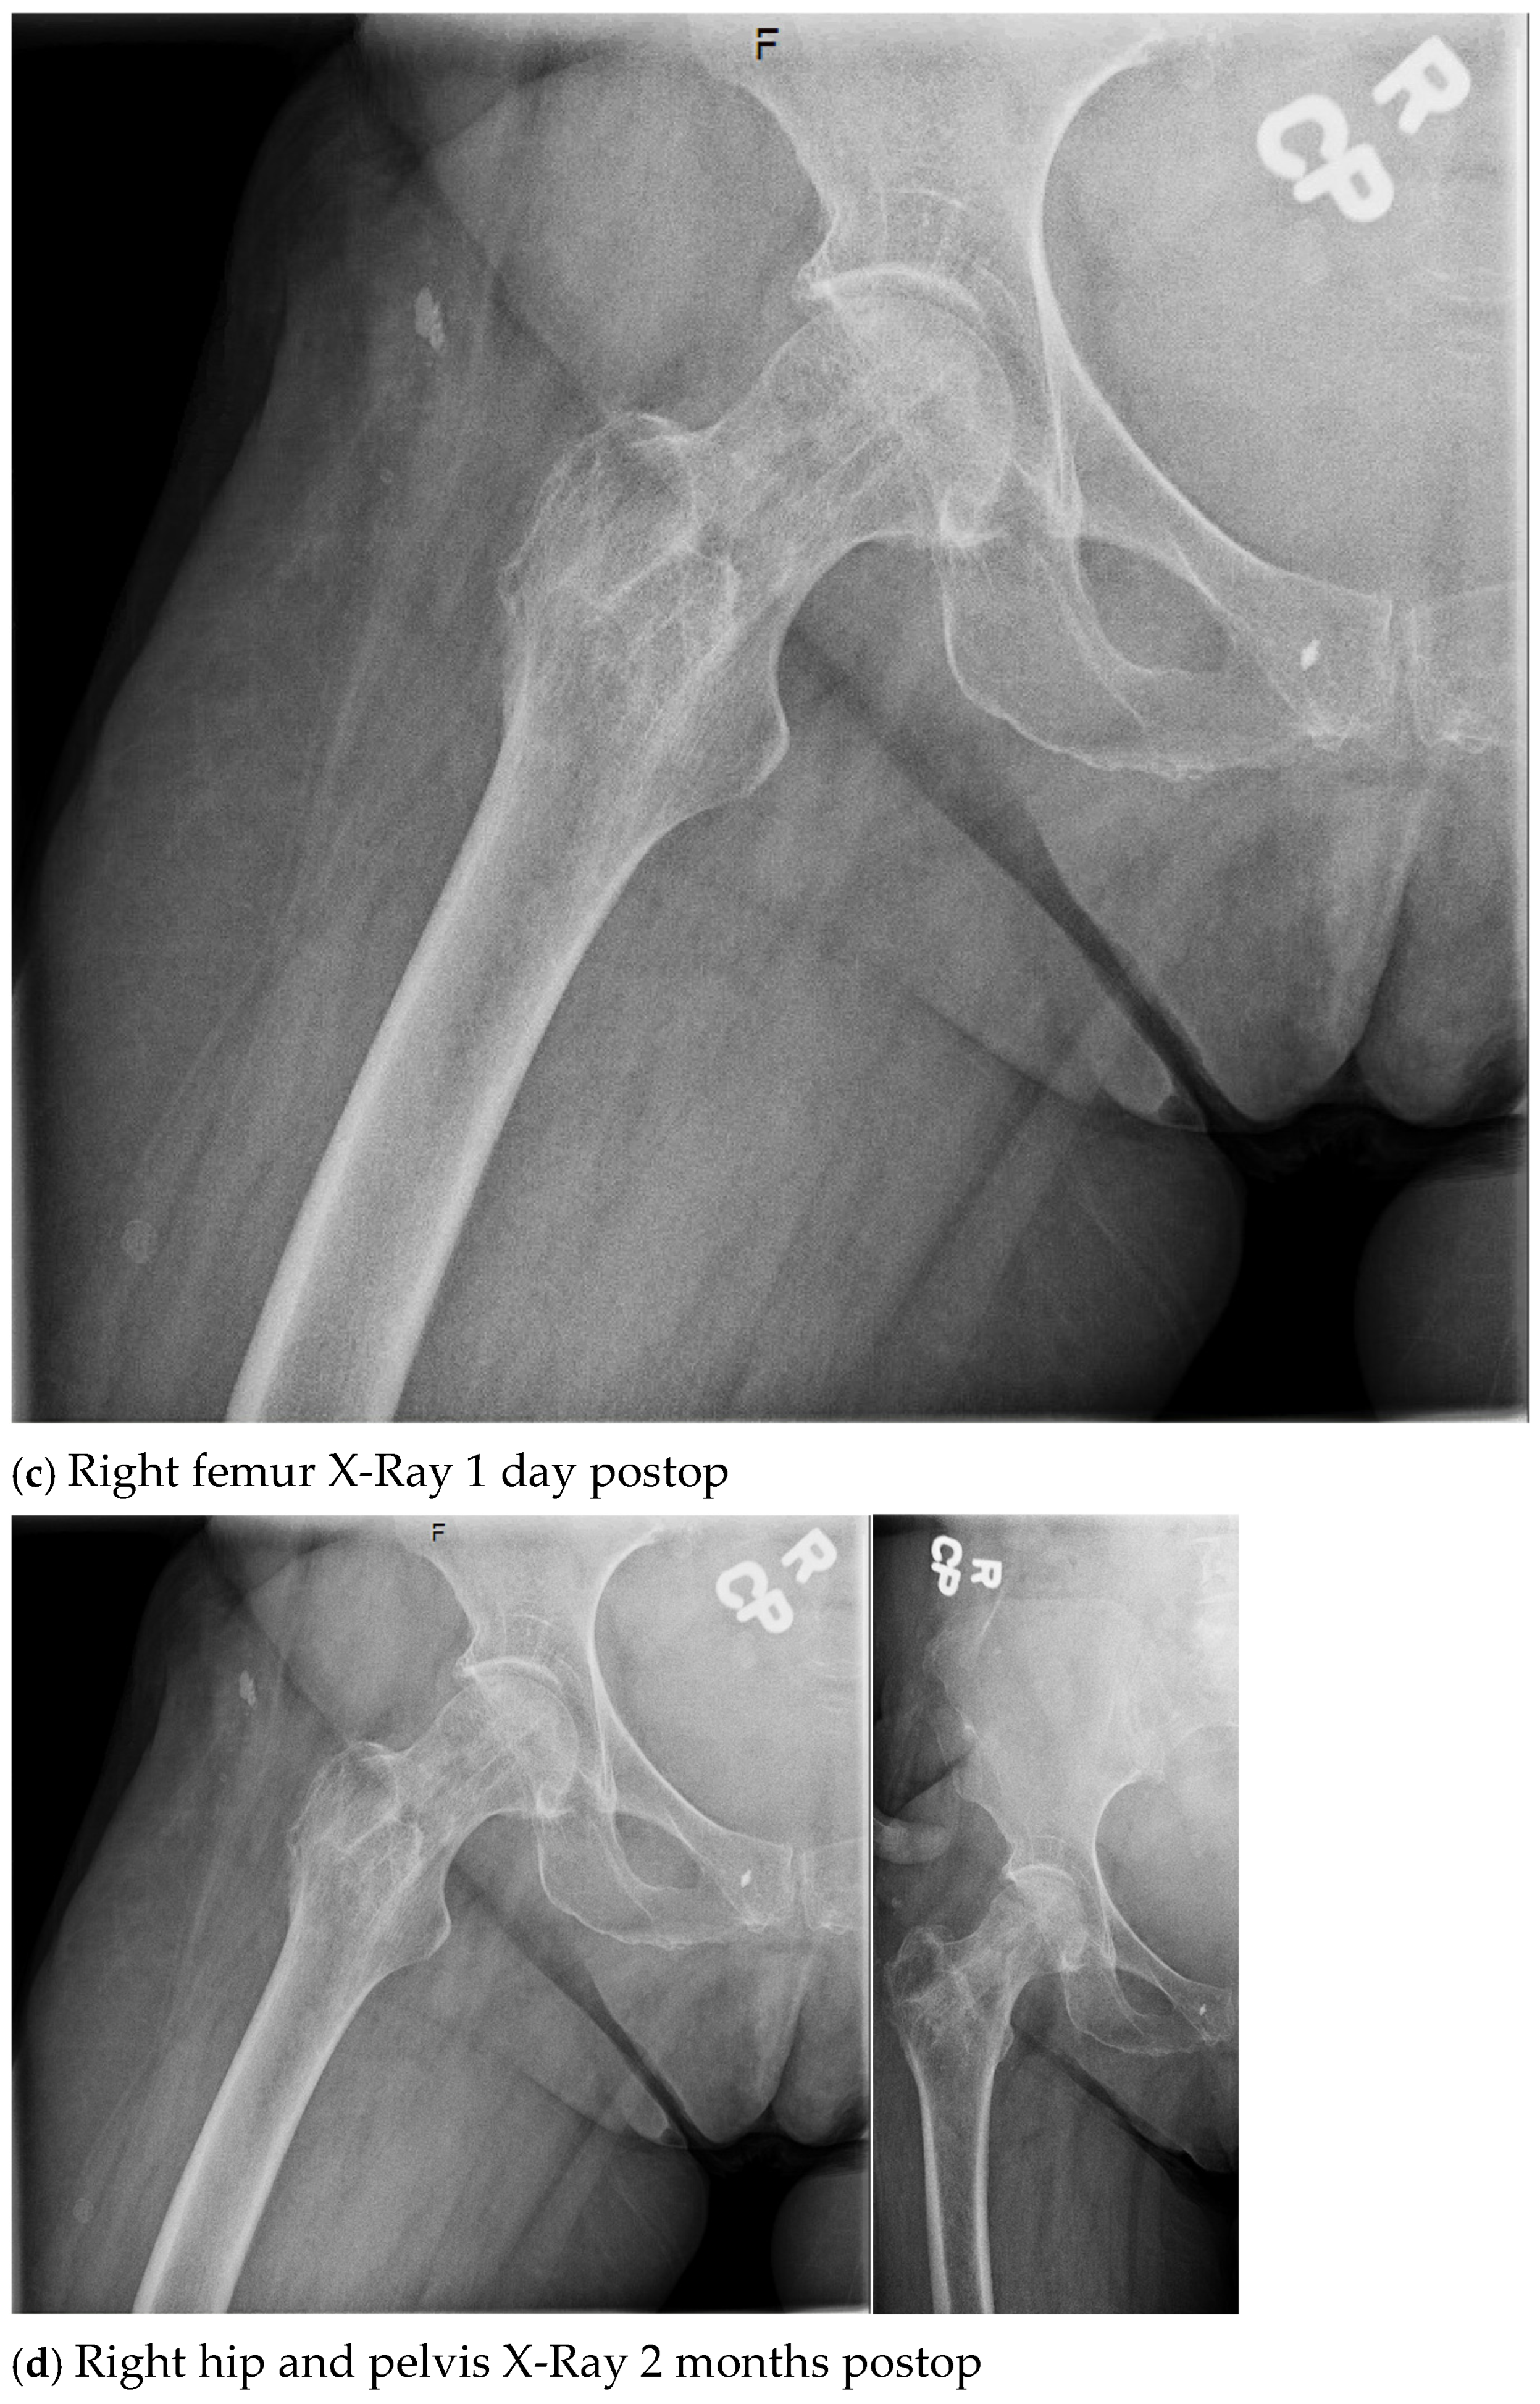

| 4. | 75 | F | Y | N | 20 | N | N | 17 | Right thigh and gluteal abscess with infected right femoral neck hardware and osteomyelitis |

| 4. | N | N | 14 | 4 | Y, clinical and lab | 107 | Negative |